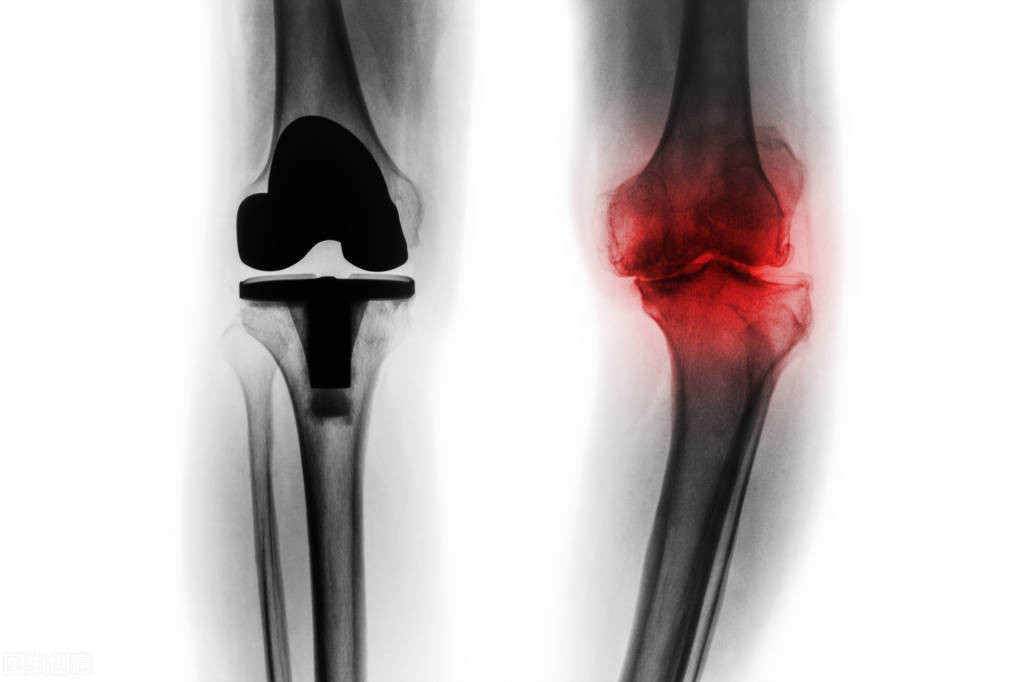

如果得了膝关节的骨关节炎,首选治疗方法应该是药物的保守治疗。如果保守治疗无效怎么办?医生可能经常会建议患者做人工膝关节置换,人工膝关节置换简单地讲,就是把整个膝关节磨损的关节面去掉,然后在两边各加上一个人工的关节面,用人工的材料相互摩擦来缓解疼痛。

针对一个年轻的,对关节活动的要求很高的病人,早期的过早地去做人工膝关节置换合适吗?应该说不完全合适,因为就像我们建造一个房子,它的一个小部分结构出现了损坏以后,我们难道要把这房子全部推掉重新盖吗?其实完全没有必要,我们只要把房子做一个小的修缮,就可以继续使用了。同理,针对早期膝关节炎这样的病人,临床上还有一个新的治疗方法,叫做膝关节周围截骨术。

如果我们仔细观察一下,可以发现罹患了膝关节骨关节炎的病人,他的腿经常是有畸形的,最常见的畸形是O型腿畸形,也就是膝关节内翻畸形,内翻畸形是什么原因导致的呢?首先肯定是关节内侧间隙的磨损,还有一个更重要的因素,是膝关节周围股骨的远端,或者胫骨近端的内翻畸形,而且最常见的是胫骨近端的内翻畸形,这个时候其实我们只需要把胫骨近端的内翻畸形,选择在一个合适的位置把胫骨截断,截断以后,我们把出现内翻的畸形向外侧矫正,到一个合适的理想位置以后,内侧用一个钢板把胫骨固定起来,让胫骨重新愈合,这样就会让本来偏向内侧的负重力线,通过截骨矫形以后转移到了外侧,大大的减轻了膝关节内侧间隙的压强,从而缓解了关节的疼痛。